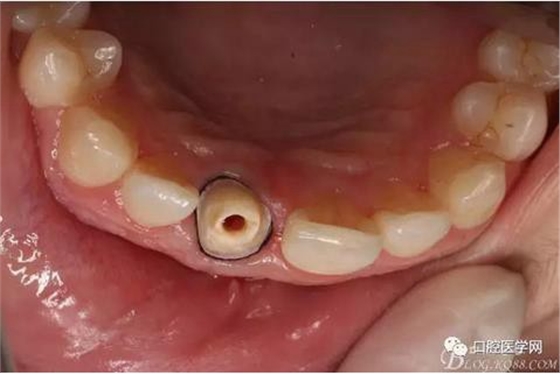

檢查:11殘根,烤瓷冠脫落,部分充填材料和折斷的纖維樁存于內(nèi)冠。唇側(cè)牙齦紅腫,基牙肩臺(tái)在齦下2毫米,根尖區(qū)觸診無(wú)不適,黏膜無(wú)紅腫,無(wú)瘺管口。叩診(-)??谇逍l(wèi)生一般。

纖維樁+樹(shù)脂核

樁道長(zhǎng)14mm